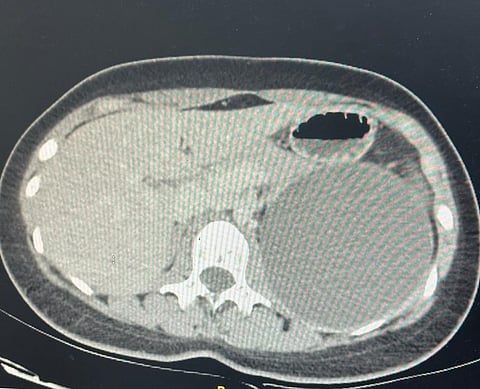

وكانت الشابة تعاني آلاماً شديدة في الجانب الأيسر من البطن، وبعد إجراء الفحوصات اللازمة، اكتشف الأطباء وجود ورم كبير بحجم 10×10 سم فوق الغدة الكظرية اليسرى.

وتمكن الفريق الطبي باستخدام المنظار الجراحي، من استئصال الورم الكيسي بشكلٍ كاملٍ، مع الحفاظ على الغدة الكظرية والكلية اليسرى سليمتَيْن.